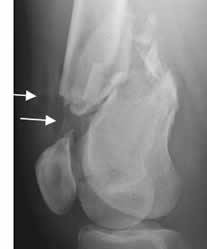

Fig 47. Fractura diastasada.

A: y B: Rx lateral. Fracturas conminutas, rotadas y diastasadas en las diáfisis femorales.